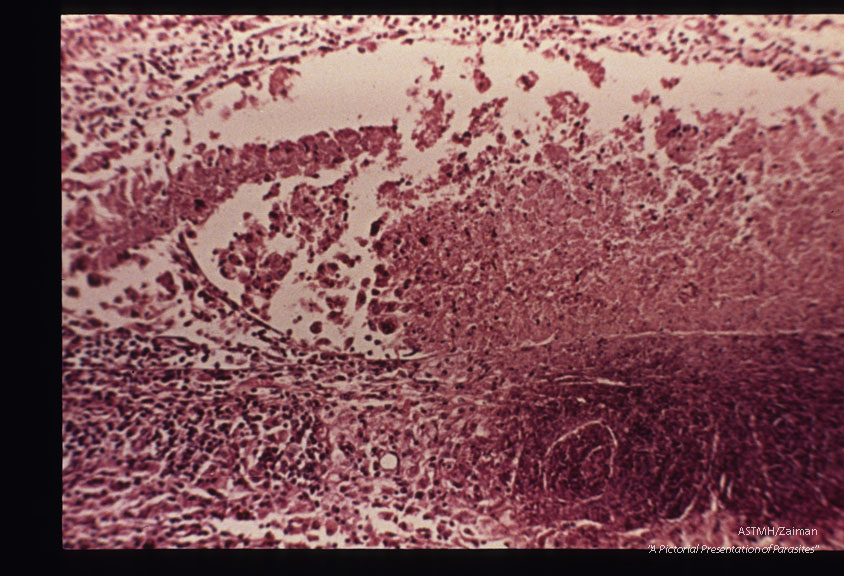

Zonal granuloma in retina.

Toxoplasma gondii

Description: Zonal granuloma in retina.